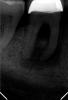

Михалыч007 Опубликовано 24 мая, 2012 Поделиться Опубликовано 24 мая, 2012 после 3 месяцев ведения зуба на кальцийсодержащих препаратов зуб запломбирован гуттаперчей( видно разницу в структуре костной ткани-она начала восстанавливаться) 1 Ссылка на комментарий

Михалыч007 Опубликовано 24 мая, 2012 Поделиться Опубликовано 24 мая, 2012 ещё одномоментная пломбировка зуба гуттаперчей Ссылка на комментарий